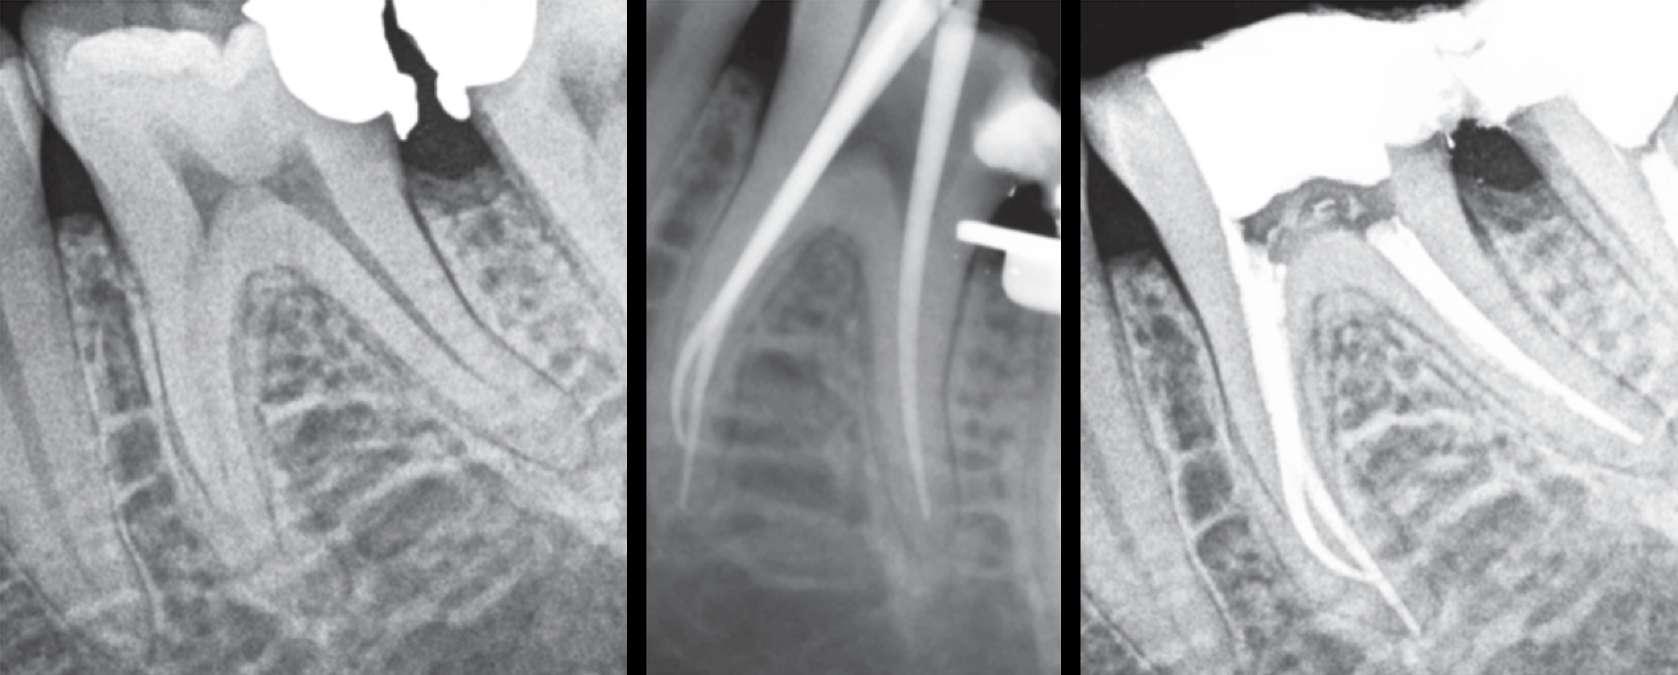

Das präoperativ angefertigte diagnostische Röntgenbild zeigt eine insuffiziente Amalgamfüllung im distalen Approximalraum. Die mesiale Wurzel weist eine periapikale Osteolyse auf (Abbildung 1).

Die endodontische Behandlung fand in einer Sitzung statt. Nach Anästhesie und Anlegen des Kofferdams erfolgte die Entfernung der provisorischen Füllung und die initiale intrakoronale Diagnostik. Mittels Microopener konnte ein mesiobukkaler, mesiolingualer, distobukkaler und distolingualer Wurzelkanal sondiert werden. Die Ausarbeitung der primären Zugangskavität zur besseren Zugänglichkeit der Kanäle erfolgte mit Langschaftrosenbohrern. Anhand des präoperativen diagnostischen Röntgenbilds konnte die Länge der Wurzelkanäle vorläufig näherungsweise bestimmt werden. Die Kanäle wurden im weiteren Therapieverlauf kontinuierlich mit 6% NaOCl gespült. Nach Ausarbeitung der Zugangskavität folgte die koronale Erweiterung der Wurzelkanäle mit EdgeEndo X7 Feilen der Größe 17.06. Die elektrometrische Bestimmung der Kanallänge mithilfe eines Morita Root ZX Mini Apex Locators wurde mit C-Piloten der Größe 8-10 durchgeführt. Nach Festlegung der Arbeitslänge wurde der

Gleitpfad rotierend mit EdgeFile X7 der Größe 17.04 und 25.04 erweitert und final bis auf 30.04 aufbereitet (Abbildung 2).

Abbildung 1: Präoperative Diagnostische Aufnahme

Abbildung 2: Blick auf das mesiale Kanalsystem nach Präparation

Abbildung 3: Ansicht nach Obturation Abbildung 4: Masterpointaufnahme Abbildung 5: Nach Wurzelfüllung und adhäsivem Verschluss